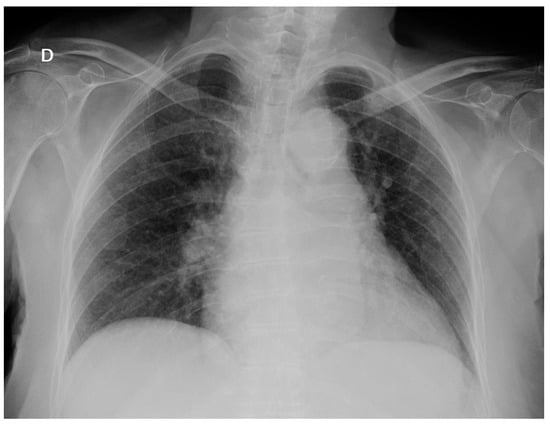

At admission, she was febrile (39 °C), eupneic with oxygen saturation 99%, a blood pressure of 125/85 mmHg, with a pulse rate of 86 bpm, arrhythmic, and a breath rate of 14 bpm. Physical exams revealed no abnormalities. At emergency department evaluation, laboratory work-up results were as follows: 6300 leukocytes with 80% neutrophils, erythrocytes count, platelets count, electrolytes and biochemistry tests were normal except for glycemia: 155 mg/dl, natremia: 123 nmol/L and C-reactive protein: 87 mg/dl. Urine analysis: 100 leukocytes and 10 erythrocytes per high-power field. Chest X-ray: normal without pulmonary infiltrates (Figure 1).

Figure 1.

Chest X-ray on admission: there are no infiltrates or opacities.